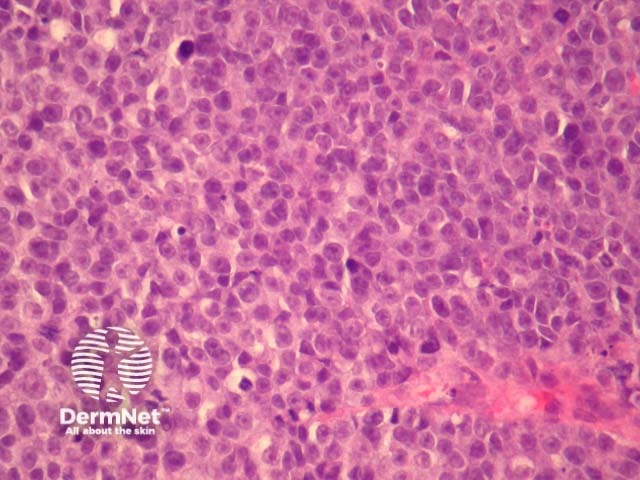

Cutaneous metastasis of melanoma can cause diagnostic confusion. The metastatic melanoma may invade the dermis or subcutis and form a nodular tumour mass without invasion of the overlying epidermis (figure 1). The pattern of growth may mimic a benign intradermal naevus at low power (figure 1) but at high power examination the nuclear atypia is usually obvious, there may be mitoses and there is minimal evidence of maturation (decrease in cell size) with descent in the dermis (figure 2). Usually the lack of epidermal involvement is a good clue the tumour is a metastasis from another site but sometimes the metastasis may invade the epidermis and closely simulate a primary melanoma.

Figure 1